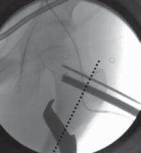

16. On the AP image the guide pin needs to be sufficiently proximal (superior) to provide enough room to permit the introduction of the seating chisel inferior to the guide pin (

TECH FIG 2A

).

17. On the frog-leg lateral view, the guide pin should lie in the middle of the femoral neck in line with the neck axis (

TECH FIG 2B

--- TECH FIG 2 • Intraoperative C-arm–guided insertion of the seating chisel for the blade plate.A. Insertion of the guide pin in the superior part of the neck at right angles to the long axis of the femur. B. Position of the guide pin along the midfemoral neck axis in the frog-leg lateral view. C. Position of the seating chisel parallel to the guide pin and perpendicular to the long axis of the femur. D. Position of the seating chisel parallel to the guide pin and along the midfemoral neck axis on the frog-leg lateral view. E. The seating chisel is backed out from its final position to disimpact the chisel before the osteotomy.Pr FiAE